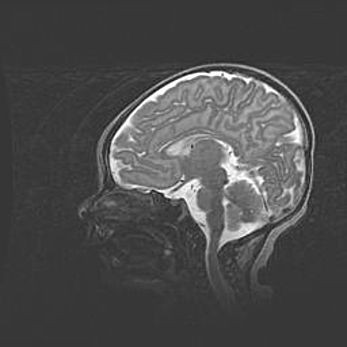

Церебральная ишемия II.

Возраст: 5 дней

Вес: 3400 г

Пол: женский

Окружность головы: 35 см

Срок гестации: 39 недель

Церебральная ишемия – это заболевание, характеризующееся недостаточностью (гипоксией) либо полным прекращением (аноксией) снабжения мозга кислородом по причине закупорки одного или нескольких сосудов. Это приводит к  что метаболическим расстройствам различной степени тяжести в тканях головного мозга, развитию коагуляционных некрозов и гибели нейронов.